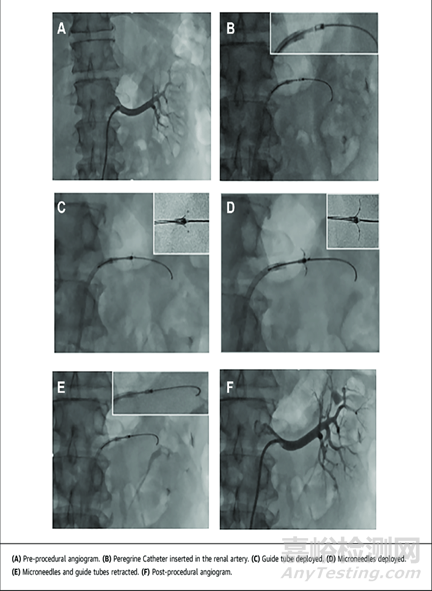

Peregrine System Infusion Catheter使用方法

Ablative Solutions 公司旗下的Peregrine微注射導(dǎo)管消融系統(tǒng)通過股動(dòng)脈進(jìn)入腎動(dòng)脈,通過導(dǎo)管末端的三根微針向腎動(dòng)脈外膜注射 0.3~0.6ml 的 96-98%脫水乙醇,以損傷血管外神經(jīng)的方式實(shí)現(xiàn)去腎交感神經(jīng)支配。其注射導(dǎo)管的安全性與有效性試驗(yàn)自 2014年7月起,2017年9月結(jié)束,并且被美國(guó)FDA 批準(zhǔn)用于向外周血管周圍輸注診斷和治療藥物,已于2015年5月獲得CE認(rèn)證用于進(jìn)行腎動(dòng)脈神經(jīng)消融治療難治性高血壓患者。目前運(yùn)用于治療高血壓的Peregrine System 有兩項(xiàng)試驗(yàn)在進(jìn)行中,TARGET BP OFF-MED臨床試驗(yàn)和 TARGET BP I 臨床試驗(yàn)均在美國(guó)和歐洲進(jìn)行。TARGET BP I 臨床試驗(yàn)正在積極招募患者。由于化學(xué)消融包括無水酒精尚未在腎臟系統(tǒng)有過治療其他任何疾病的先前案例,因此FDA對(duì)這一器械有著額外的臨床安全性的證據(jù)要求,需要有數(shù)百例額外患者隨訪較長(zhǎng)時(shí)間以證明其安全性。

這是一篇2020年發(fā)表在《美國(guó)心臟病雜志》上的文章。45例接受3種降壓藥物治療的高血壓患者,使用Peregrine導(dǎo)管進(jìn)行雙側(cè)腎去神經(jīng)支配,每條腎動(dòng)脈注入0.6毫升酒精。與基線相比,6個(gè)月時(shí)24小時(shí)動(dòng)態(tài)血壓的收縮壓平均降低為-11mmHg,舒張壓平均降低至-7mmHg,6個(gè)月時(shí),診室收縮壓降低了-18/-10mmHg。高血壓藥物在6個(gè)月時(shí)減少了23%,96%的患者達(dá)到了主要安全終點(diǎn),即在1個(gè)月內(nèi)沒有圍手術(shù)期主要血管并發(fā)癥、大出血、急性腎損傷或死亡。兩名患者出現(xiàn)了圍手術(shù)期進(jìn)入部位假性­動(dòng)脈瘤的重大不良事件,其中一名患者出現(xiàn)大出血。沒有死亡或心肌梗死、中風(fēng)、短暫性腦缺血發(fā)作或腎動(dòng)脈狹窄。

本試驗(yàn)的初步結(jié)果表明,使用Peregrine導(dǎo)管進(jìn)行酒精介導(dǎo)的腎去神經(jīng)支配可以安全地降低血壓,可能是治療高血壓的一種新方法。

血管造影圖像